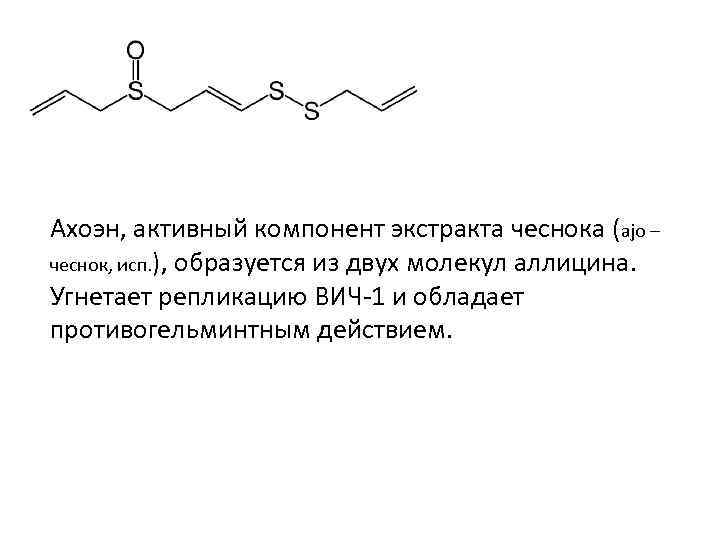

Ахоэн, активный компонент экстракта чеснока (ajo – чеснок, исп. ), образуется из двух молекул аллицина. Угнетает репликацию ВИЧ-1 и обладает противогельминтным действием.